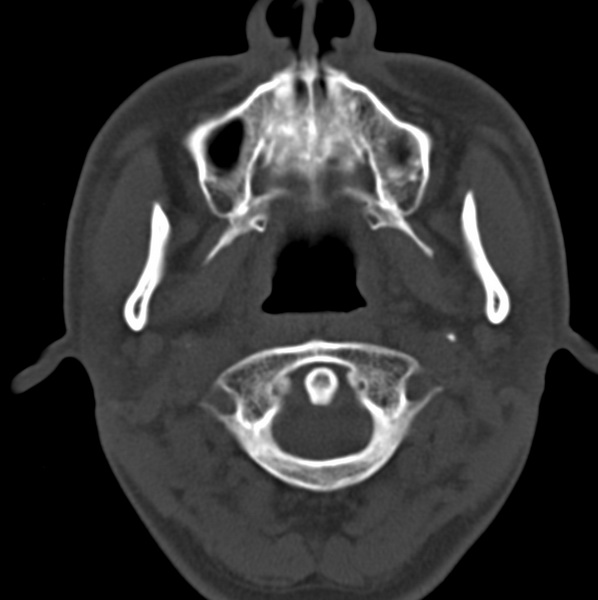

男、31、鼻咽部肿瘤放疗后请帮忙看看。

效果好,右侧破裂孔扩大,局部骨质缺损,为颅底骨质破坏。

1)鼻咽部肿瘤侵犯颅底放疗术后改变。2)左侧蝶窦炎。

咽后壁增厚,左侧咽鼓管隆突增大、咽鼓管咽口变浅,同侧咽旁间隙较窄。右侧颅底骨质破坏?为什么不在同一侧?

鼻咽部肿瘤侵犯颅底放疗术后改变.